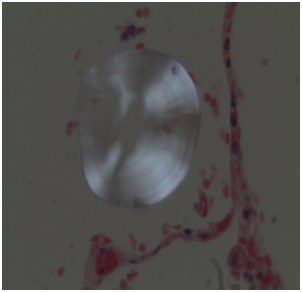

Histology: Acute emphysema was the prominent observation; edema and hemorrhages were also present.4 In 9 cases (Figures 3-6), exogenous material in the airways, comprehensive of planktonic boli in the lower branches, clearly demonstrable at polarization microscope (and possibly confirmable at SEM’s elemental analysis with EXD). Zoo- and phytoplankton have been better identified in the UV microscope. It is mandatory to differentiate the planktonic material from gastric content, regurgitated and aspirated (Figure 7 & 8).

Figures 3,4 Drowning in seawater. Images of endoalveolar zooplankton (protoconch of crustacean) (EE, 480 X, polarized light).